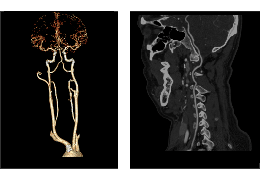

成像智能。

Eclipse 成像智能功能提供强大的处理能力和最佳质量的影像,同时减少质量错误并提高剂量效率。

凭借 AI、专有算法和先进的影像处理能力,提供出色的影像质量和无与伦比的诊断信心。

与标准影像处理相比,智能降噪功能可使客户降低辐射剂量,而不会损失影像质量。这在新生儿和儿科成像中尤其重要,在这种情况下以尽可能低的剂量成像至关重要。

提供相配视图选项,以减少所需的曝光次数,并提供更清晰的感兴趣区域视图。